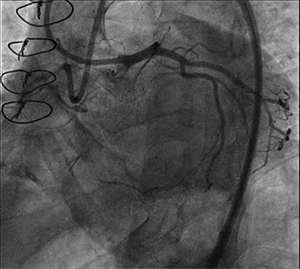

Take this case as an example. A 65-year-old man with progressive dyspnea on optimal medical therapy, ischemic cardiomyopathy, and prior coronary artery bypass with occluded grafts was referred for intervention of the RCA. Initial dual injection showed an undefined proximal cap and long CTO, with epicardial collaterals from the circumflex artery (figure 1). Antegrade wire escalation and retrograde wiring were unsuccessful; thus, subintimal dissection reentry was attempted. Despite multiple attempts, the reentry device unfortunately was unable to break into the true lumen. At that point, the decision was made to perform balloon angioplasty of the subintimal space from distal to proximal as an “investment” for a future PCI reattempt.

Figure 1. Initial dual injection